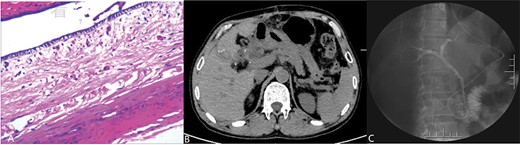

The patient is a 53-year-old man who was admitted to the hospital due to recurrent episodes of vague epigastric pain over a 4-month period. The patient had been diagnosed with Choledochal cysts and pancreatic pseudocyst in a local hospital before coming to seek treatment in our hepatological surgery department. Clinical evaluation revealed no yellowing of the skin or sclera, no abdominal wall varices, a soft abdomen without tenderness, and no abnormal masses felt. The liver and spleen were not palpable. The routine laboratory tests also were unremarkable. CT scan (Fig. 1A) showed cystic dilation lesion of the extrahepatic bile duct, which the largest one ~6.3 × 5.6 cm, and a mass of mixed density shadow in the pancreatic body and tail that measuring ~10.3 × 7.8 cm. MRI and MRCP (Fig. 1B) revealed multiple cystic dilation lesions in the common bile duct, which was considered as Choledochal cyst type I and a pseudocyst forming in the body and tail of the pancreas. ERCP (Fig. 1C) revealed that there is not dilation of the bile ducts and the cystic duct was partially developed, but the gallbladder was not developed. A multidisciplinary consultation was conducted by the hepatological surgery department in collaboration with the radiology department and endoscopy unit. The diagnosis is suspected to be a cystic lesion at the hepatoduodenal ligament, and it has been decided to perform preoperative ERCP followed by nasobiliary tube placement.

(Postoperative image) A: Pathological examination revealed a cyst with a fibrous wall, dense chronic inflammatory infiltration; B: CT after operation; C: Radiography through nose-bile tube after operation.